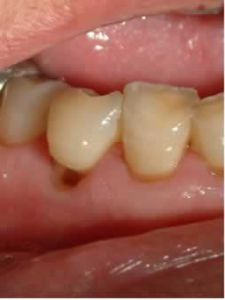

(三)按病變深度分類淺齲分為窩溝齲和平滑面齲。窩溝齲的齲損部位色澤變黑,用探針檢查時有粗糙感或能鉤住探針尖端。平滑面齲一般呈白堊色、黃褐色或褐色斑點。患者一般無主觀症狀,對冷、熱、酸、甜刺激亦無明顯反應。中齲的齲洞已形成,洞內牙本質軟化呈黃褐或深褐色。患者對酸甜飲食敏感,過冷過飲食也能產生酸痛感覺,冷刺激尤為顯著,但刺激去除後症狀立即消失。頸部牙本質齲的症狀較為明顯。深齲的齲洞深大,位於鄰面的深齲洞,外觀略有色澤改變,洞口較小而病損破壞很深。如食物嵌入洞中,可出現疼痛症狀。遇冷、熱和化學刺激時,產生的疼痛較為劇烈。